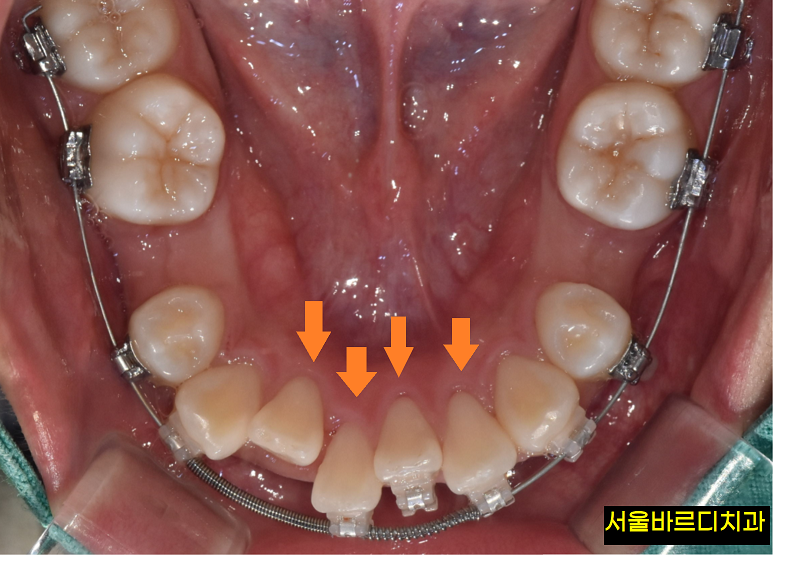

치아 교정 스프링이 적용된 사진입니다.

보시면 아래 앞니 치아가

옹기 종기 모여있죠?

치열을 고르게 정렬하기 위해 공간을 확보해야 할 때

오픈 코일을 사용합니다.